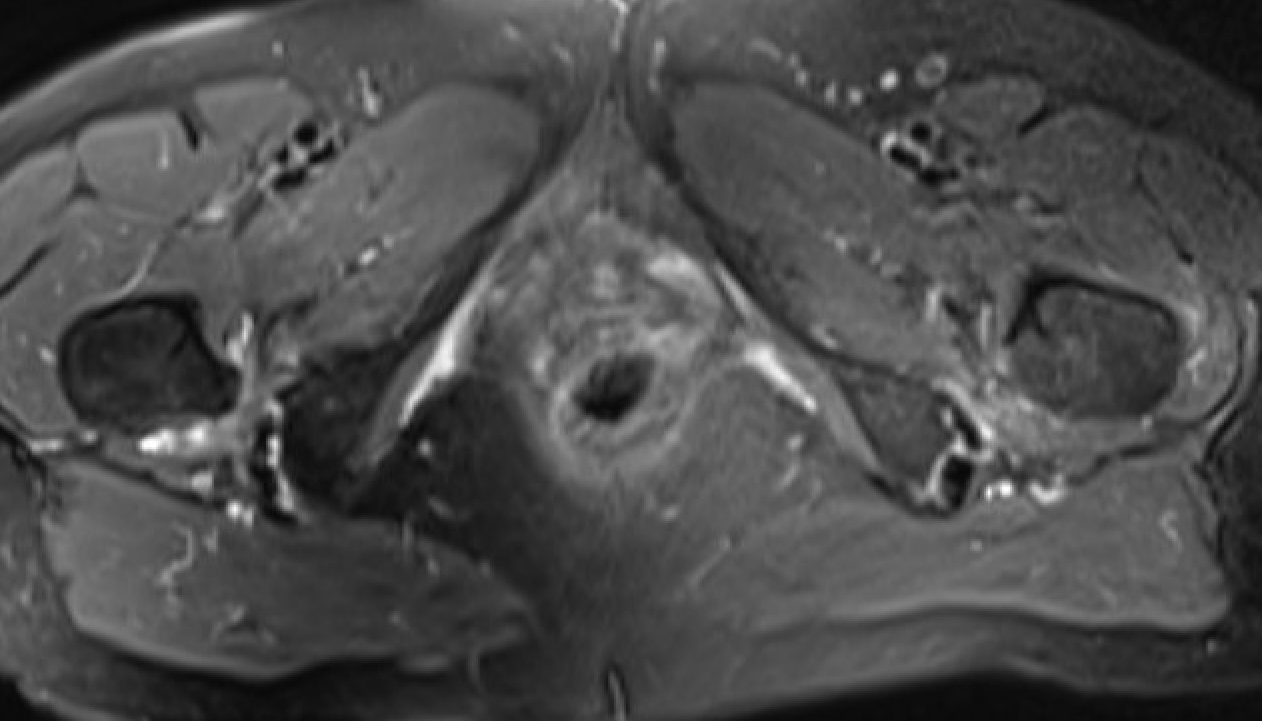

MRI

Reduced ischiofemoral space - distance between the lesser trochanter and the ischial tuberosity

Reduced quadratus femoris space - distance between hamstring tendon and iliopsoas

Inflammation / edema in quadratus femoris +/- fatty degeneration